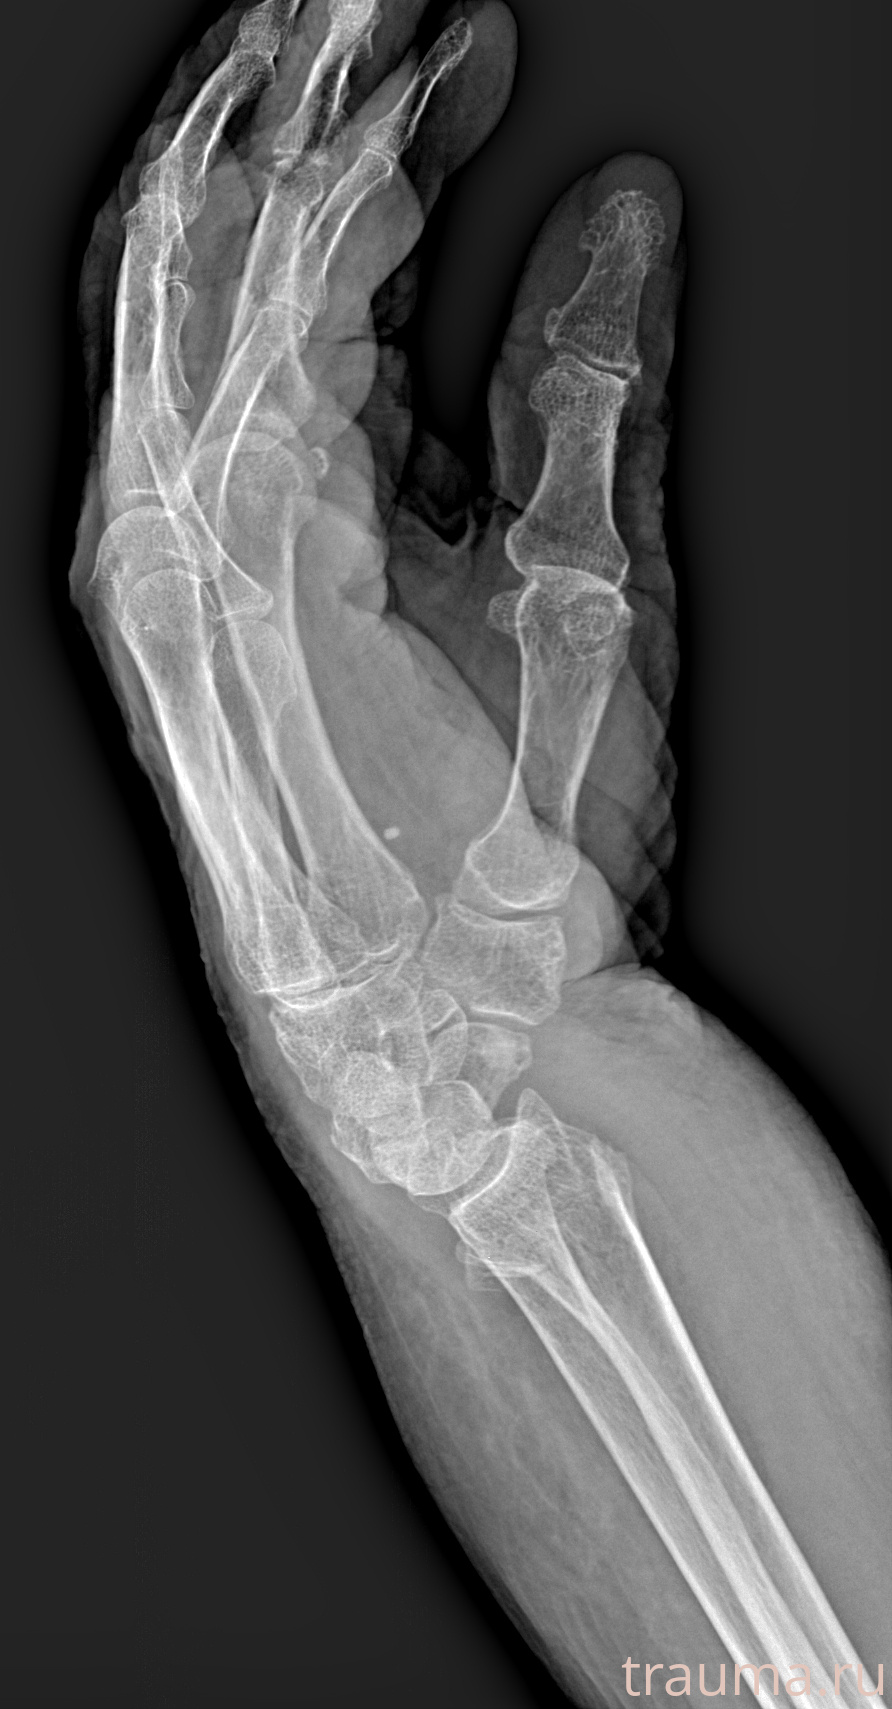

Рентген на дому: по вашему адресу приезжает врач-рентгенолог, травматолог-ортопед с мобильным рентгеновским аппаратом, проводит диагностику травмы или заболевания, делает необходимые рентгенограммы, дает рекомендации по дальнейшему лечению. Получить качественные снимки в домашних условиях возможно благодаря уникальной методике, разработанной МосРентген Центром для института  Склифосовского